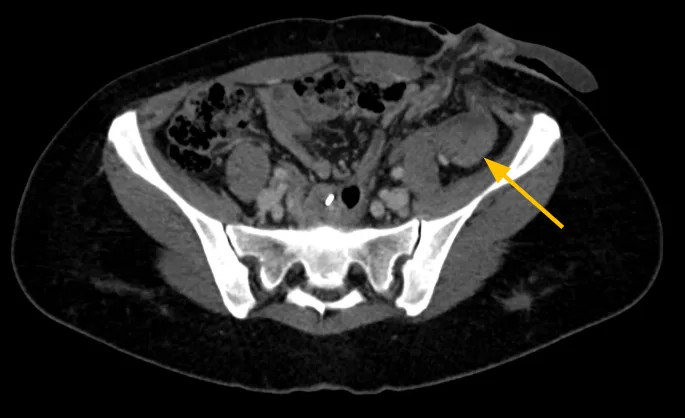

Derivação urinária em alça delgada na fossa ilíaca à esquerda. Houve boa distensão da alça de derivação, porém nota-se falha de enchimento de aspecto polipoide na fase excretora medindo cerca de 2,2 x 1,0 cm. Sugere-se prosseguir investigação.

- Lesão polipoide na alça ileal da derivação urinária